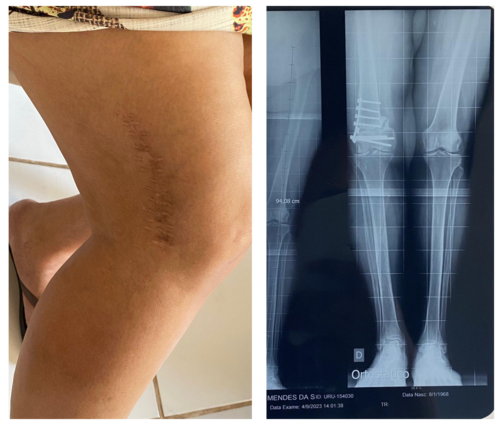

Há 1 ano e 6 meses minha mãe Eliana Maria Mendes da Silva passou por uma cirurgia de Osteotomia no joelho direito, devido a uma artrose muito avançada, mas infelizmente as placas, ou seja, os parafusos não se consolidaram e ficou uma diferença na perna direita. Hoje ela precisa colocar uma prótese de correção no joelho, pois além das terríveis dores, ela está com muita dificuldade para andar.

O SUS não cobre essa prótese, pois ela tem 55 anos, e precisa ser uma prótese importada. A cirurgia precisa ser feita com urgência, pois está forçando muito o seu joelho esquerdo, e o mesmo já está com complicações da artrose também, bem como o pé esquerdo que já passou por uma intervenção cirúrgica pelo agravamento da artrose. Ela não consegue levar uma vida normal, pois tem limitações para andar e fazer seus afazeres diários.